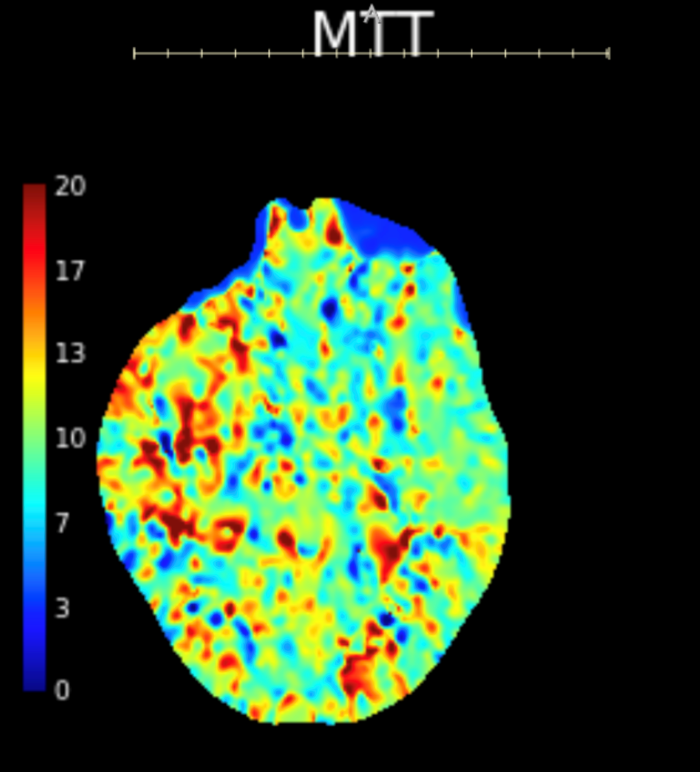

Initial objective data included T 37C, HR 85, RR 20, BP 153/109, spO2 98%. Glucose 102. Basic labs obtained and were unremarkable. Patient was rapidly taken to CT for stroke imaging. No contraindications to thrombolytics were identified. At 1708, noncontrast head CT showed no hemorrhage, but an abnormal hypodensity along the right middle cerebral artery concerning for an air embolus was visualized. CT angiogram head and neck was also suggestive of air embolus and CT perfusion brain demonstrated 27 mL of critical hypoperfusion at the right posterior middle cerebral artery distribution.

Figure 3: CT perfusion brain showing prolonged mean transit time in the right MCA distribution compared to the left MCA.

Figure 4: CT perfusion brain showing calculated 27 ml area of critical hypoperfusion with >6 seconds time-to-maximum filling.